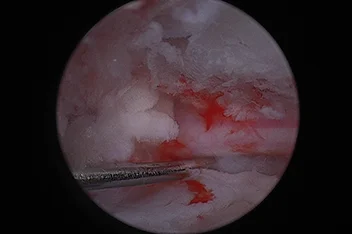

부울경 최초 ‘양방향 척추내시경’ 도입

정밀하고 덜 아픈 척추 수술의 새로운 패러다임

양방향 척추 내시경 BESS, Biportal Endoscopic Spine Surgery

기존의 단일 포털 내시경(uniportal endoscopy)의 한계를 극복한

정밀한 양손 작업이 가능한 최소침습 기술입니다.

리본동물의료센터 2025년 1월부터 부울경 최초로 양방향 척추 내시경을 도입해왔으며, 영남권 최다 임상 CASE를 축적하고 있습니다.

양방형 척추 내시경 수술의 핵심 장점

• 정밀한 수술 조작

• 근육 인대 손상 최소화

• 절개 최소화

• 빠른 회복과 낮은 통증

• 고배율 직시 시야 확보

양방형 척추 내시경 수술 전

양방형 척추 내시경 수술 후